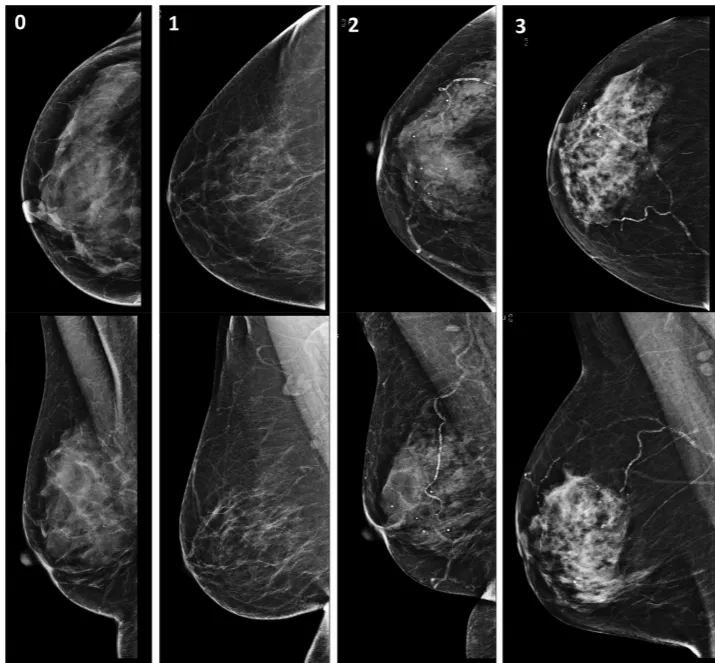

Breast arterial calcification on mammography and risk of coronary artery disease: a SCOT-HEART sub-study Image Link to paper on Clinical Radiology. Authors S. McLenachan, F. Camilleri, M. Smith, D.E. Newby, M.C. Williams Abstract Aim: To assess the prevalence of breast arterial calcification (BAC) in patients who also underwent routine surveillance mammography, and to determine the association with cardiovascular risk factors, coronary artery calcification, and coronary artery disease on coronary computed tomography angiography (CCTA). Materials and methods: Four hundred and five female participants were identified who had undergone CCTA and subsequent mammography in the SCOT-HEART randomised controlled trial of CCTA in patients with suspected stable angina. Mammograms were assessed visually for the presence and severity of BAC. Results: BAC was identified in 93 (23%) patients. Patients with BAC were slightly older (63±7 versus 59±8 years, p<0.001), with a higher cardiovascular risk score (19±11 versus 16±10, p=0.022) and were more likely to be non-smokers (73% versus 49%, p<0.001). In patients with BAC, coronary artery calcification was present in 58 patients (62%; relative risk [RR] 1.26, 95% confidence intervals [CI]: 1.04, 1.53; p=0.02), non-obstructive coronary artery disease in 58 (62%; RR 1.27, 95% CI: 1.04 to 1.54, p=0.02), and obstructive coronary artery disease in 19 (20%; RR 1.62, 95% CI: 0.98, 2.66; p=0.058). Patients without BAC were very unlikely to have severe coronary artery calcification (negative predictive value 95%) but the diagnostic accuracy of BAC to identify coronary artery disease was poor (AUC 0.547). Conclusion: Although BAC is associated with the presence and severity of coronary artery calcification, the diagnostic accuracy to identify patients with coronary artery disease or obstructive coronary artery disease is poor. Keywords Breast arterial calcification (BAC) Mammography Coronary artery calcification Coronary artery disease Coronary computed tomography angiography (CCTA) Related links Link to paper on Clinical Radiology Link to paper on Clinical Radiology Issue Highlights Professor David Newby Dr Michelle Williams Heart / cardiovascular SCOT-HEART Publication date 15 May, 2019